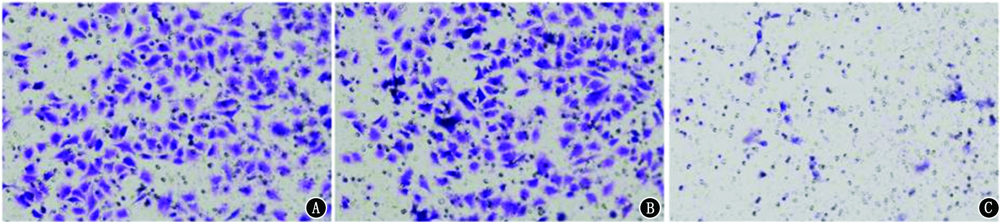

目的 探讨活化T细胞核因子5(NFAT5)在肺腺癌组织及细胞中的表达以及抑制NFAT5对肺腺癌细胞增殖、侵袭、迁移及凋亡能力的影响。方法 收集2017年6月至2019年6月在解放军联勤保障部队第九〇四医院接受诊断和治疗的61例肺腺癌患者的临床病理标本和癌旁组织,采用实时荧光定量PCR(qRT-PCR)检测肺腺癌组织、癌旁组织中NFAT5的表达水平,并分析NFAT5的表达水平与患者临床病理特征的关系。将H1975细胞分为对照组(不作任何处理)、NC组(转染siRNA-NC)和si-NFAT5组(转染siRNA-NFAT5),采用qRT-PCR检测细胞株中NFAT5的表达水平,采用MTT和克隆形成实验检测细胞增殖情况,Transwell和划痕实验检测细胞侵袭和迁移能力,流式细胞仪检测细胞凋亡情况,蛋白质印迹法检测细胞丝裂原活化蛋白激酶(MAPK)信号通路相关蛋白的表达。结果 NFAT5 mRNA在肺腺癌组织中的表达量(3.22±0.20)显著高于癌旁组织(1.00±0.12),差异具有统计学意义(t=75.662,P<0.001);肺腺癌组织中NFAT5的表达水平与肿瘤TNM分期(χ2=10.357,P=0.001)和淋巴结转移(χ2=18.268,P<0.001)有关。NFAT5在对照组、NC组、si-NFAT5组中的相对表达量分别为1.00±0.06、1.01±0.05、0.31±0.06,差异具有统计学意义(F=140.498,P<0.001)。对照组、NC组和si-NFAT5组3组H1975细胞转染24 h后吸光度(A)值分别为0.70±0.01、0.55±0.01、0.35±0.01,48 h后分别为0.92±0.03、0.87±0.06、0.57±0.06,72 h后分别为1.05±0.01、0.90±0.01、0.66±0.01,差异均具有统计学意义(F=9.815,P=0.013;F=45.977,P<0.001;F=129.494,P<0.001),进一步两两比较,24、48、72 h si-NFAT5组增殖能力均明显低于对照组和NC组(均P<0.001)。3组细胞克隆数分别为452.33±31.50、421.00±17.35、129.00±17.35,差异具有统计学意义(F=128.200,P<0.001);si-NFAT5组细胞克隆数较对照组和NC组均显著下降(均P<0.001)。3组细胞侵袭数目分别为262.67±28.02、278.00±27.50、46.00±12.00,差异具有统计学意义(F=89.896,P<0.001);si-NFAT5组细胞侵袭能力较对照组和NC组均显著降低(均P<0.001)。3组细胞相对划痕宽度分别为0.28±0.04、0.32±0.04、0.54±0.04,差异具有统计学意义(F=42.889,P<0.001);si-NFAT5组细胞相对划痕宽度较对照组和NC组均显著增加(均P<0.001)。3组细胞凋亡率分别为(3.38±0.56)%、(3.14±0.62)%、(13.82±0.75)%,差异具有统计学意义(F=264.705,P<0.001);si-NFAT5组细胞凋亡率均显著高于对照组和NC组(均P<0.001)。3组H1975细胞NFAT5、p-P38/P38、p-ERK1/2/ERK1/2、p-JNK/JNK蛋白表达差异均具有统计学意义(F=91.245,P<0.001;F=132.896,P<0.001;F=243.332,P<0.001;F=118.358,P<0.001);si-NFAT5组NFAT5、p-P38/P38、p-ERK1/2/ERK1/2、p-JNK/JNK蛋白表达较对照组和NC组均显著降低(均P<0.001)。结论 NFAT5在肺腺癌组织及细胞中的表达均升高。抑制NFAT5能够抑制肺腺癌H1975细胞增殖、侵袭和迁移,并促进H1975细胞凋亡,其机制可能与NFAT5抑制MAPK信号通路有关。

Objective To investigate the expressions of nuclear factor of activated T cell 5 (NFAT5) in lung adenocarcinoma tissues and cells, and the effects of NFAT5 on the proliferation, invasion, migration and apoptosis of lung adenocarcinoma cells. Methods The clinical pathological specimens and paracancerous tissues of 61 patients with lung adenocarcinoma diagnosed and treated in 904th Hospital of Joint Logistic Support Force of People's Liberation Army from June 2017 to June 2019 were collected. The expression levels of NFAT5 in lung adenocarcinoma tissues and paracancerous tissues were detected by quantitative real-time PCR (qRT-PCR), and the relationships between the expression of NFAT5 and clinicopathological features of patients were analyzed. H1975 cells were divided into control group (no treatment), NC group (transfecting siRNA-NC) and si-NFAT5 group (transfecting siRNA-NFAT5) . qRT-PCR was used to detect the expression level of NFAT5 in cell line. MTT and clone formation assay were used to detect cell proliferation. Transwell and scratch test were used to detect cell invasion and migration ability. Flow cytometry was used to detect cell apoptosis. The expressions of mitogen-activated protein kinase (MAPK) signaling pathway related proteins were detected by Western blotting. Results The expression level of NFAT5 mRNA in lung adenocarcinoma (3.22±0.20) was significantly higher than that in paracancerous tissues (1.00±0.12), and there was a statistically significant difference (t=75.662, P<0.001). The expression level of NFAT5 in lung adenocarcinoma tissue was associated with TNM stage (χ2=10.357, P=0.001) and lymph node metastasis (χ2=18.268, P<0.001). The expression levels of NFAT5 in the control group, NC group and si-NFAT5 group were 1.00±0.06, 1.01±0.05 and 0.31±0.06, and there was a statistically significant difference (F=140.498, P<0.001). The absorbance (A) values in the control group, NC group and si-NFAT5 group were 0.70±0.01, 0.55±0.01 and 0.35±0.01 at 24 h after transfection, 0.92±0.03, 0.87±0.06 and 0.57±0.06 at 48 h after transfection, 1.05±0.01, 0.90±0.01 and 0.66±0.01 at 72 h after transfection, and there were statistically significant differences (F=9.815, P=0.013; F=45.977, P<0.001; F=129.494, P<0.001). Further pairwise comparison showed that the proliferation abilities of the si-NFAT5 group at 24, 48 and 72 h were significantly lower than those of the control group and NC group (all P<0.001). The cell clone numbers in the three groups were 452.33±31.50, 421.00±17.35 and 129.00±17.35 respectively, with a statistically significant difference (F=128.200, P<0.001). The cell clone number in the si-NFAT5 group was significantly lower than that in the control group and NC group (both P<0.001). The invasion numbers of cells in the three groups were 262.67±28.02, 278.00±27.50 and 46.00±12.00 respectively, and there was a statistically significant difference (F=89.896, P<0.001). The cell invasive ability in the si-NFAT5 group was significantly lower than that in the control group and NC group (both P<0.001). The relative scratch widths in the three groups were 0.28±0.04, 0.32±0.04 and 0.54±0.04 respectively, and there was a statistically significant difference (F=42.889, P<0.001). The relative scratch width in the si-NFAT5 group was significantly increased than that in the control group and NC group (both P<0.001). The apoptosis rates in the three groups were (3.38±0.56)%, (3.14±0.62)% and (13.82±0.75)% respectively, and there was a statistically significant difference (F=264.705, P<0.001). The apoptosis rate in the si-NFAT5 group was significantly higher than that in the control group and NC group (both P<0.001). The differences of protein expressions of NFAT5, p-P38/P38, p-ERK1/2/ERK1/2, p-JNK/JNK among the three groups were statistically significant (F=91.245, P<0.001; F=132.896, P<0.001; F=243.332, P<0.001; F=118.358, P<0.001). The protein expressions of NFAT5, p-P38/P38, p-ERK1/2/ERK1/2, p-JNK/JNK in the si-NFAT5 group were all significantly lower than those in the control group and NC group, and there were statistically significant differences (all P<0.001). Conclusion The expression of NFAT5 is increased in lung adenocarcinoma tissues and cells. Inhibition of NFAT5 can inhibit proliferation, invasion and migration of lung adenocarcinoma H1975 cells, and promote apoptosis of H1975 cells. The mechanism may be related to the inhibition of MAPK signal pathway by NFAT5.